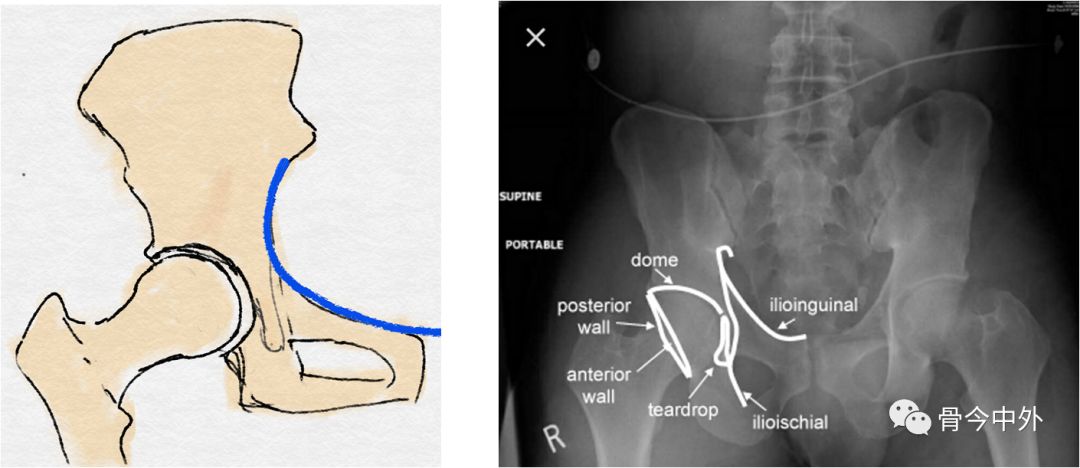

3、骨盆连续性的评估

髂耻线:

连接髂骨内缘与耻骨上缘的弧线

反映髋臼前柱、骨盆前环的完整性

髂坐线:

连接髂骨内缘与坐骨内缘的弧线

反映髋臼内壁、四边体的完整性

泪滴:

U型的弧线

代表了髋臼的内缘

前唇线:

髋臼前缘所连成的弧线(左图中蓝线)

反映髋臼前壁的完整性

后唇线:

髋臼后缘所连成的弧线(左图中红线)

反映髋臼后壁的完整性